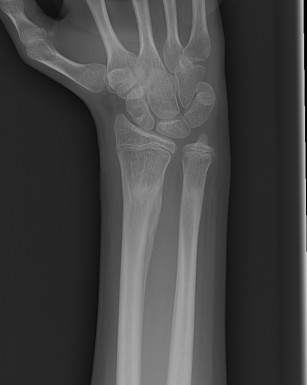

Visible deformity

> 20o angulation

Mercer Rang Remodelling Rules

Best if

- young age (won't remodel much if > 11 years)

- short distance from fracture to physis

- direction of angulation in plane of motion of joint

Won't correct rotation

Rang distal radius remodelling

- < 5 - 25-35°

- 4 - 9 - 20-25

- 10-12 - < 15°